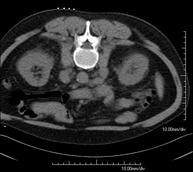

Prova diagnòstica no invasiva que consisteix en l'estudi de l'artèria aorta abdominal a través de l'obtenció d'imatges d'alta definició anatòmica mitjançant l'ús d'un equip de TC (Tomografia Computeritzada) i de contrast iodat. La qualitat de les imatges permet realitzar reconstruccions en 2D i 3D gràcies a estacions de treball especialitzades en l'estudi arterial. Està indicat en aquells pacients amb malaltia vascular (arteriosclerosi), en aneurismes d'aorta, en pacients amb dolor abdominal de possible origen vascular, en estudis prequirúrgics de lesions adjacents a l'aorta abdominal com a "mapa" vascular. La informació obtinguda de manera no invasiva és indispensable per als pacients que requereixen tractament percutani o quirúrgic. En aquells pacients que només requereixen seguiment de les lesions vasculars, aquesta tècnica és la tècnica no invasiva d'elecció juntament amb l'angio-RM. - Angio-TC Artèries renals

Prova diagnòstica no invasiva que consisteix en l'estudi de les artèries ilíaques i l'aorta abdominal a través de l'obtenció d'imatges d'alta definició anatòmica mitjançant l'ús d'un equip de TC (Tomografia Computeritzada) i de contrast iodat. La qualitat de les imatges permet realitzar reconstruccions en 2D i 3D gràcies a estacions de treball especialitzades en l'estudi arterial. Aquesta prova està especialment indicada com estudi prequirúrgic (mapa vascular) abans d'intervencions percutànies o quirúrgiques d'aorta abdominal, com l'estudi complementari en pacients amb isquèmia de membres inferiors, etc. - Colonoscòpia virtual

Prova diagnòstica no invasiva que consisteix en l'estudi de l'artèria aorta abdominal amb l'obtenció d'imatges d'alta definició anatòmica mitjançant l'ús d'un equip de TC (Tomografia Computaritzada) i contrast iodat. La qualitat de les imatges permet realitzar reconstruccions en 2D i 3D gràcies a estacions de treball especialitzades en l'estudi arterial. Està indicat en aquells pacients que pateixen malaltia vascular (arteriosclerosi), aneurismes d'aorta, en pacient amb dolor abdominal d'un possible origen vascular, en estudis prequirúrgics de lesions adjacents a l'aorta abdominal com el "mapa" vascular, etc. La informació obtinguda de forma no invasiva és indispensable per als pacients que requereixen tractament percutani o quirúrgic. En aquells pacients que només requereixen un seguiment de les lesions vasculars, aquesta tècnica és la tècnica no invasiva d'elecció juntament amb l'angio RM. - Angio TC d'artèries renals

Prova diagnòstica no invasiva que consisteix en l'estudi de les artèries ilíaques i l'aorta abdominal amb l'obtenció d'imatges d'alta definició anatòmica mitjançant l'ús d'un equip de TC (Tomografia Computaritzada) i contrast iodat. La qualitat de les imatges permet realitzar reconstruccions en 2D i 3D gràcies a estacions de treball especialitzades en l'estudi arterial. Aquesta prova està especialment indicada com a estudi prequirúrgic (mapa vascular) abans d'intervencions percutànies o quirúrgiques d'aorta abdominal, estudi complementari en pacients amb isquèmia de membres inferiors, etc. - Angio TC arterial d'extremitats inferiors